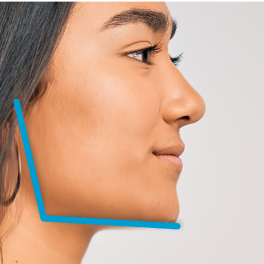

Mesofacial

“Normal or neutral” facial profile with deep overbite.